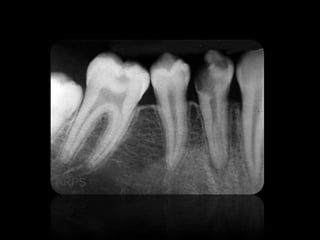

3.

• Las imagenes

son llamadas radio opacas. • Las imagenes son llamadas radio lúcidas.

CARIES